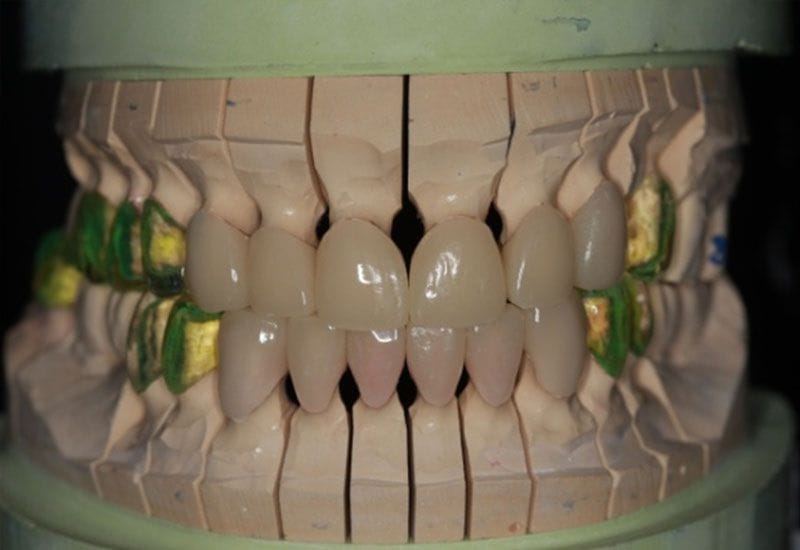

首先 假牙專科醫師先為病人訂定一個符合理論的咬合高度於咬合器上,經過全口精密分析,陳柏均醫師為蕭小姐訂下了適合他的咬合高度與上下顎的顎間關係然後做全口的蠟型設計與雕刻,並製作成臨時假牙外殼

如圖6

經過長時間1-3個月的觀察與分析 在確立新的咬合顎間關係沒有問題後,將精密印模 預備送往技工所,由專業技師製作氧化鋯全瓷冠 將其復形

如圖8.9

氧化鋯全瓷冠為牙醫師精密印模後 資深技師將牙醫師臨床印的精密模型灌模

之後,模型以電腦掃瞄 電腦分析設計 電腦磨出(CAD CAM) 即Computer aided design/Computer aided manufacturing等步驟 製作精密且耐用的氧化鋯基底全瓷冠,由於技師可以在電腦上分析並設計假牙的外型與咬合關係,大大節省與牙醫師臨床的調整且大大改善了整體全口假牙重建的精密度。

首先,在電腦軟體裡分析設計的假牙,會先以超硬壓克力輸出。陳柏均醫師將以此壓克力假牙,先於病人口內試戴,調整外型,咬合等

如圖10.11

E在陳柏均醫師精密的調整咬合與外型後,技師將再次掃瞄這些超硬壓克力假牙,將其輸入電腦中,做另一次精密修正,最後將此外型以氧化鋯材質電腦精密磨出,製作成最終氧化鋯假牙全瓷冠

如圖 12.